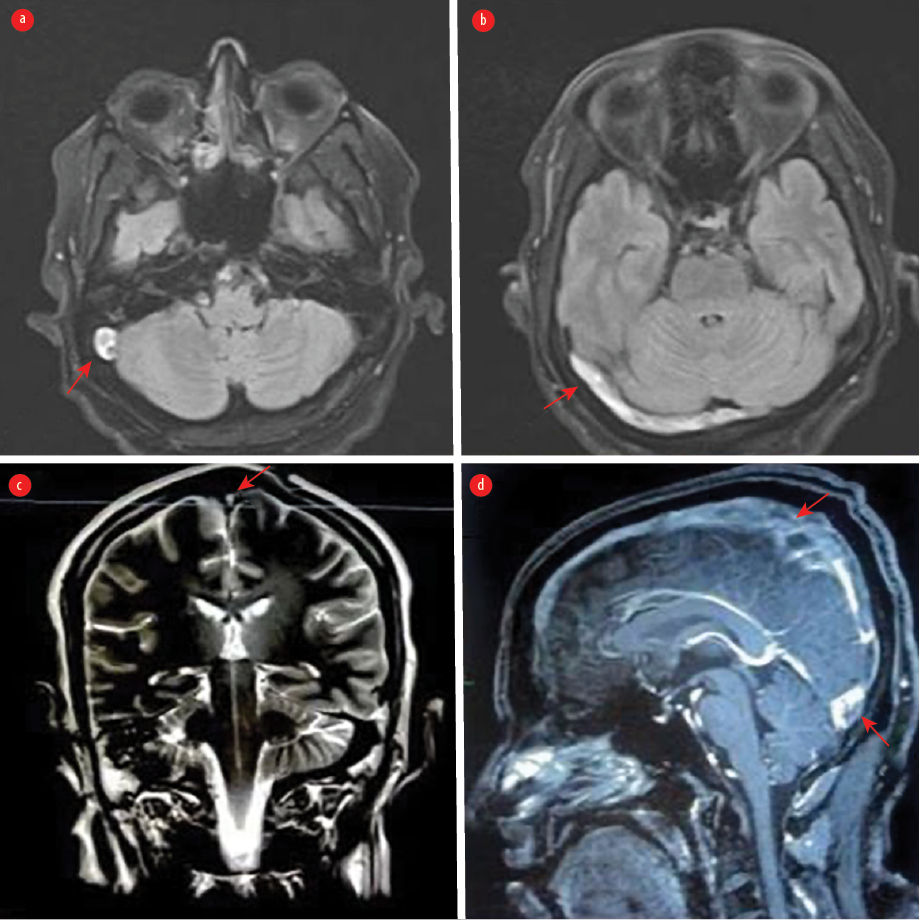

All blood tests, including the basic tests and those for vasculitis and thrombophilia, and spiral computed tomography (CT) of the chest, came back normal. A CT scan of the brain with and without contrast and CT cerebral venography revealed a picture consistent with extensive cerebral venous thrombosis (CVT) [Figure 2].

Figure 2: (a) Non-enhanced axial CT of the brain revealed hyperdense transverse sinuses on the right side as well as edema in the right occipitoparietal regions. (b) An enhanced axial CT of the brain showed an empty delta sign due to thrombosis in the superior sagittal sinus. The sign consists of a triangular area of enhancement with a low-attenuating center, which is the thrombosed sinus. (c) An axial CT venogram shows no flow in the right transverse and right sigmoid sinuses, with a filling defect due to thrombosis.